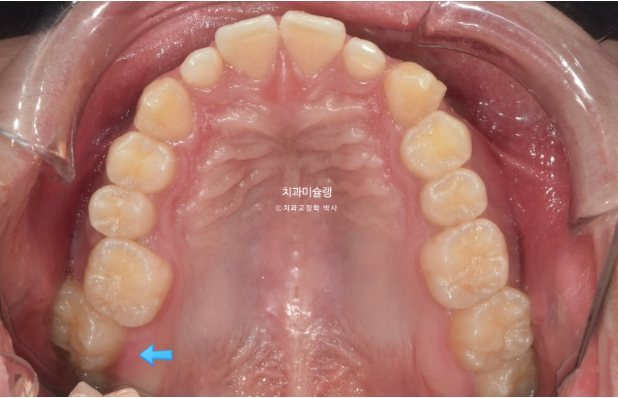

이 환자분이 한쪽으로만 씹었던 이유는 반대쪽에 가위교합이 있었기 때문입니다.

파란 화살표가 가위교합이고 위 큰어금니는 바깥으로 나가있고 대합치는 안쪽으로 쓰러지며 가위처럼 서로 엇갈려 교합되는 상태를 말합니다.

파란 화살표 치아가 바깥으로 뻗치면서 가위교합의 원인이 됩니다.

치료 목표는 치아 중심선을 얼굴중심으로 끌어오기 위해 편측 사랑니 공간을 이용한 후방이동, 이때 교정용 나사인 미니스크류가 필요하겠죠.